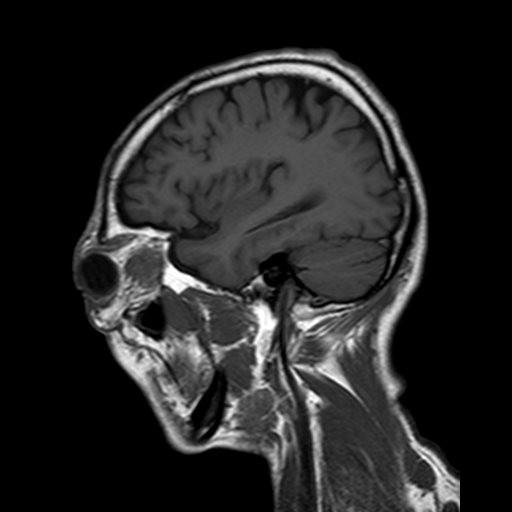

症例1:50代男性

眼瞼腫脹と視力低下を主訴に来院。眼窩内腫瘍が疑われた。

図12 造影後矢状断

図13 造影後矢状断

図14 造影後矢状断